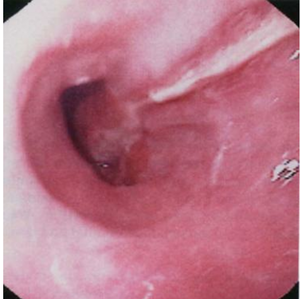

Mallory weiss tear

Oesophagitis